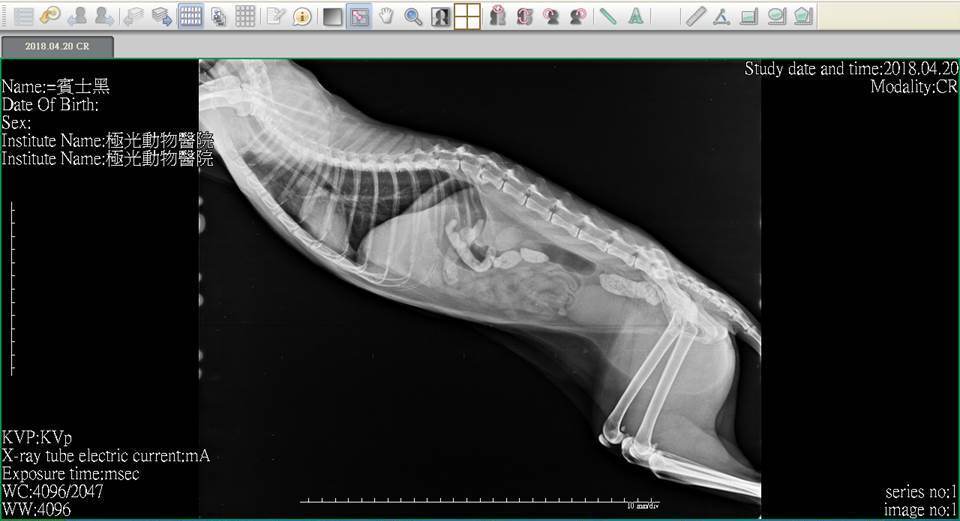

主題: 患有腎衰口炎胰臟炎的麵滷 申請者姓名: 臺北市支持流浪貓絕育計劃協會 花色: 申請日期: 2018-05-08 17:24:45 申請者部落格: 申請者臉書網址: http://admin.tnrtw.org/hospice_add.php 所在縣市/合作醫院: 台北市/極光動物醫院 治療費用: 3600元 需求人數: 8人 已結案 (2024-06-01 13:12:24) 報名人員: 劉小賢(已付款)、林小豬 x2(已付款)、Ed Tsai x5(已付款)、 候補人員: 動物病情說明: 麵滷患有腎衰、嚴重口炎、胰臟炎,這些病症都會讓牠食慾較差,除了吃藥打皮下注射,協會照護員每日都會灌食以維持牠的體力,並每週定期看診做詳細檢查,近日牠因食慾下降更多,精神不好,協會立即安排帶牠就醫,做了血檢及x光,牠的口炎情況變得更嚴重,醫生開了藥希望可以讓麵滷口炎情況好轉,就能恢復些食慾。 動物近況說明: 每週回診、服藥、每日皮下輸液、灌食、給自煮鮮食,希望可以讓牠病情穩定。